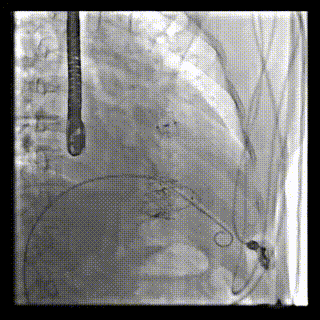

2021年12月24日,復旦大學附屬中山醫院葛均波院士團隊成功應用LuX-Valve Plus為一例極重度三尖瓣反流(TR)合并房顫、房缺的患者完成了經血管三尖瓣置換術,這是在前基礎上,本周完成的第三例經血管三尖瓣置換手術,葛均波院士、周達新教授等與心外科魏來教授、賴顥教授,心超室的潘翠珍教授、李偉教授及麻醉科的郭克芳教授共同完成了本周手術,均獲得圓滿成功!患者術后超聲顯示無TR,臨床癥狀明顯改善。本周手術的成功也為LuX-Valve Plus救治性臨床研究添上了濃墨重彩的一筆。

本周三例接受LuX-Valve Plus經血管三尖瓣置換術的患者中,第一例患者為冠狀動脈旁路移植術+Bentall+二尖瓣成形術后;第二例患者為永久起搏器植入術后,存在跨三尖瓣導線;第三例患者合并房顫、房缺及左心耳封堵術后。

三例患者入院后,葛均波院士團隊周達新教授、潘文志教授、張源博士、陳莎莎博士及心超室的潘翠珍教授、李偉教授對患者的情況進行詳細評估和討論,最終決定為三例患者選擇LuX-Valve Plus40mm、50mm和50mm型號的瓣膜進行手術治療。手術后即刻拔除氣管插管,術后患者三尖瓣反流癥狀得到顯著改善,復查心超結果顯示人工三尖瓣瓣膜支架固定穩定,瓣葉關閉形態未見異常,未見明顯反流。